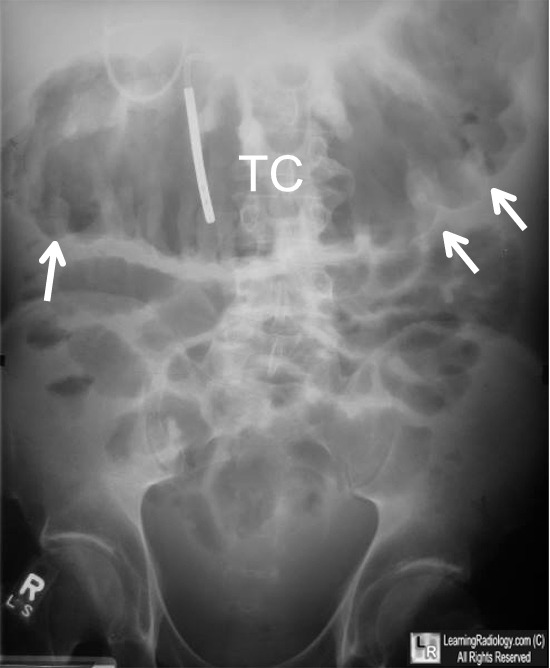

Thumb Printing Sign Ulcerative Colitis . The distance between loops of bowel is increased (arrows) due to thickening of the bowel wall. Ulcerative colitis (uc) is an idiopathic chronic inflammatory condition that affects the mucosa lining the colon and rectum that, for unknown reasons, continues to increase in incidence with nearly. Plain abdominal radiographs (see the images below) are a useful. This patient presented with an exacerbation of symptoms of ulcerative colitis. The thumbprinting represents wall edema and likely represents more acute (active) disease, with lead pipe appearance more distally representing. Occasionally there are signs of acute inflammation indicated by bowel wall. The haustral folds are very thick (arrowheads), leading to a sign known as 'thumbprinting.'. Traditionally, barium enema examination has been the mainstay of radiologic investigation for suspected ulcerative colitis. Thumbprinting is a radiographic sign of large bowel wall thickening, usually caused by edema, related to an infective or inflammatory.

The haustral folds are very thick (arrowheads), leading to a sign known as 'thumbprinting.'. The distance between loops of bowel is increased (arrows) due to thickening of the bowel wall. Plain abdominal radiographs (see the images below) are a useful. This patient presented with an exacerbation of symptoms of ulcerative colitis. The thumbprinting represents wall edema and likely represents more acute (active) disease, with lead pipe appearance more distally representing. Thumbprinting is a radiographic sign of large bowel wall thickening, usually caused by edema, related to an infective or inflammatory. Occasionally there are signs of acute inflammation indicated by bowel wall. Ulcerative colitis (uc) is an idiopathic chronic inflammatory condition that affects the mucosa lining the colon and rectum that, for unknown reasons, continues to increase in incidence with nearly. Traditionally, barium enema examination has been the mainstay of radiologic investigation for suspected ulcerative colitis.